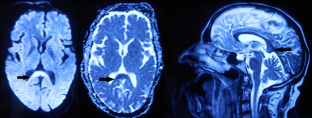

Chikungunya infection presenting as mild encephalitis with a reversible lesion in the splenium: a case report

Chikungunya fever is an Aedes mosquito-transmitted infection caused by chikungunya virus, an RNA virus in the family Togaviridae. The disease is characteristically manifested as fever, arthralgia, and/or rash. Various neurological manifestations like meningoencephalitis, myelitis, and myeloneuropathy have been mentioned in various reports. We present a rare case of chikungunya fever presenting with mild encephalitis with a reversible lesion of the splenium (MERS), which showed complete clinical and radiological recovery.

Fig. 1